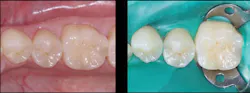

Figure 4: Final prep (left) and acid placed for selective etch of enamel only (right). Liner was not placed in this prep. Etch-and-rinse (total-etch), selective, and self-etch techniques have been shown to be adequate.

Figure 5: Glutaraldehyde placed for two one-minute applications and suctioned off (left) followed by your choice of bonding agent (right)